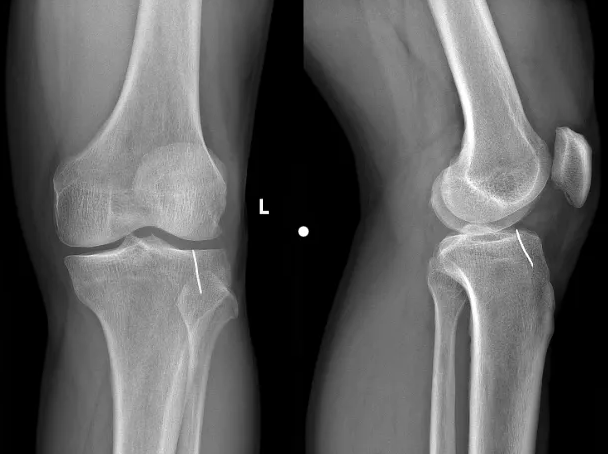

• 【强基提质】铁钉隐匿藏膝间,微创技术除疾患

近日,我院骨伤科接诊了一名因使用割草机不慎被铁钉刺伤的患者,科室团队成员迅速组织病例讨论,制定手术方案,通过膝关节镜下异物取出术,仅用30分钟成功将铁钉取出。